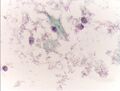

صورة مجهرية لمسحة عنق الرحم عادية